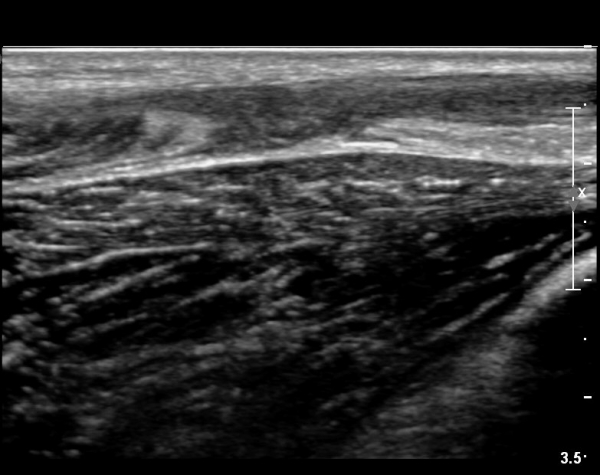

[¹ß¸ñ] simultaneosus tear of GCM and achiles tendon

abrupt leg pain developed during foot volleyball

he walk with severe limping with no weight bearing on rt. leg. on examination, there is local tendernes at GCM and achiles tendon, severe pain with ankle dorsiflexion.

ÃÊÀ½ÆÄ °Ë»ç

rec) short leg splint with crutch gait. he refused splint, then visit other hospital and took operation.